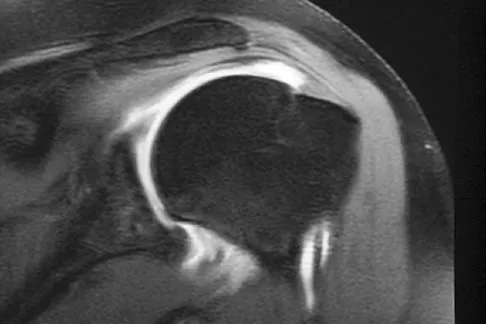

A 40-year-old right hand-dominant construction worker has had a 6-month history of aching left shoulder pain that is worse after working a long day. Examination reveals limited range of motion and good strength when compared to his asymptomatic right arm. He has not had any orthopaedic intervention to date. Radiographs are shown in Figures 43a and 43b. What is the most appropriate treatment?